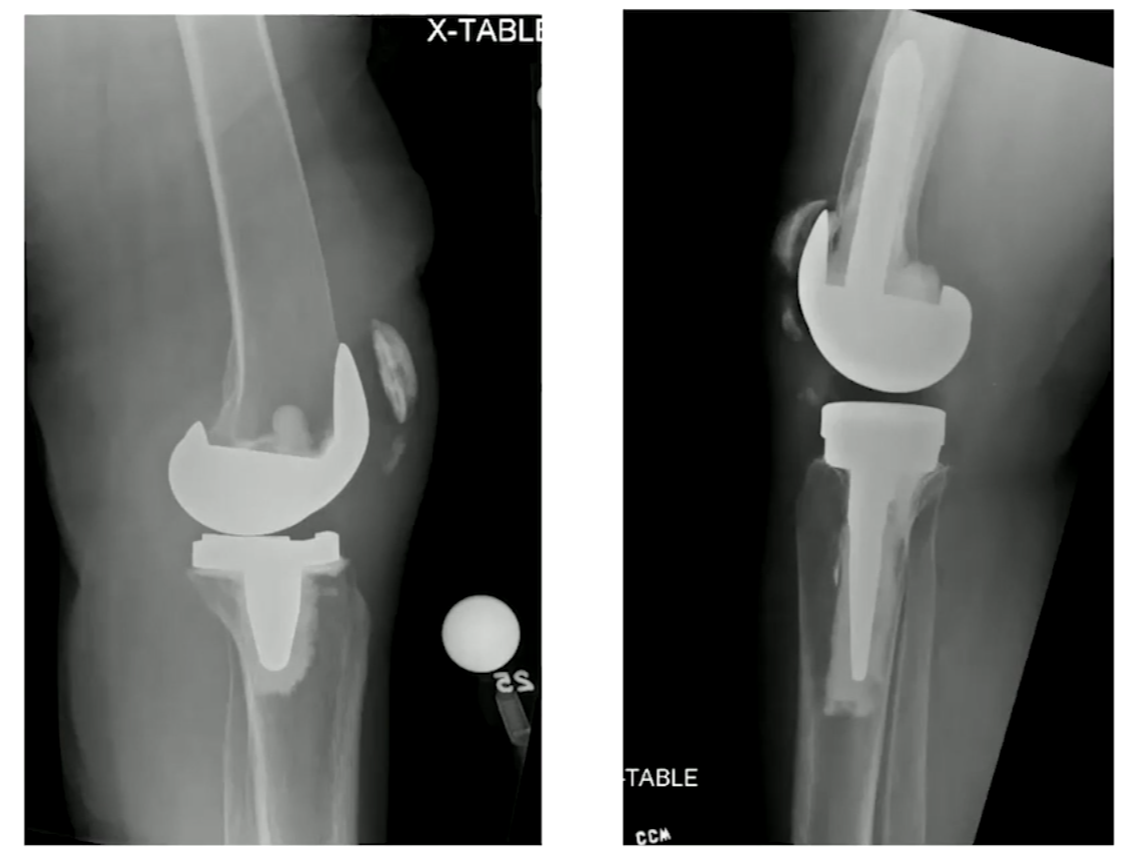

중요한 것은 Type II 인데, 폄근의 기능을 상실하였기 때문에 수술적인 치료가 필요합니다. 안에 들어간 implant는 정상일 수도 있으며, Bone Stock 이 남아있는 정도를 확인하여 수술의 종류를 설정할 수 있습니다. (대게 고령에 뼈 상태가 좋을 수 없으니 Partial patellectomy를 가장 많이 할 것 같습니다.)

아래와 같은 방식으로 여러가지 수술을 시행해 볼 수 있습니다. (ORIF, 뼈와 근육을 연결한 부위를 채취하여 기존의 patella 부분과 tibia 부분을 연결하도록 꼬매서 폄근육을 재건하는 경우, Suture anchor를 이용해서 repair 하는 경우, K-wire를 이용한 tension band wiring을 시행해 볼 수 있습니다.)

심하게 골절이 있는 경우는 슬개골을 재거하는 것 까지 생각해야 합니다.

Type III의 경우 골질의 양에 따라 두개로 선택지를 나누어 치료를 할 수 있습니다.